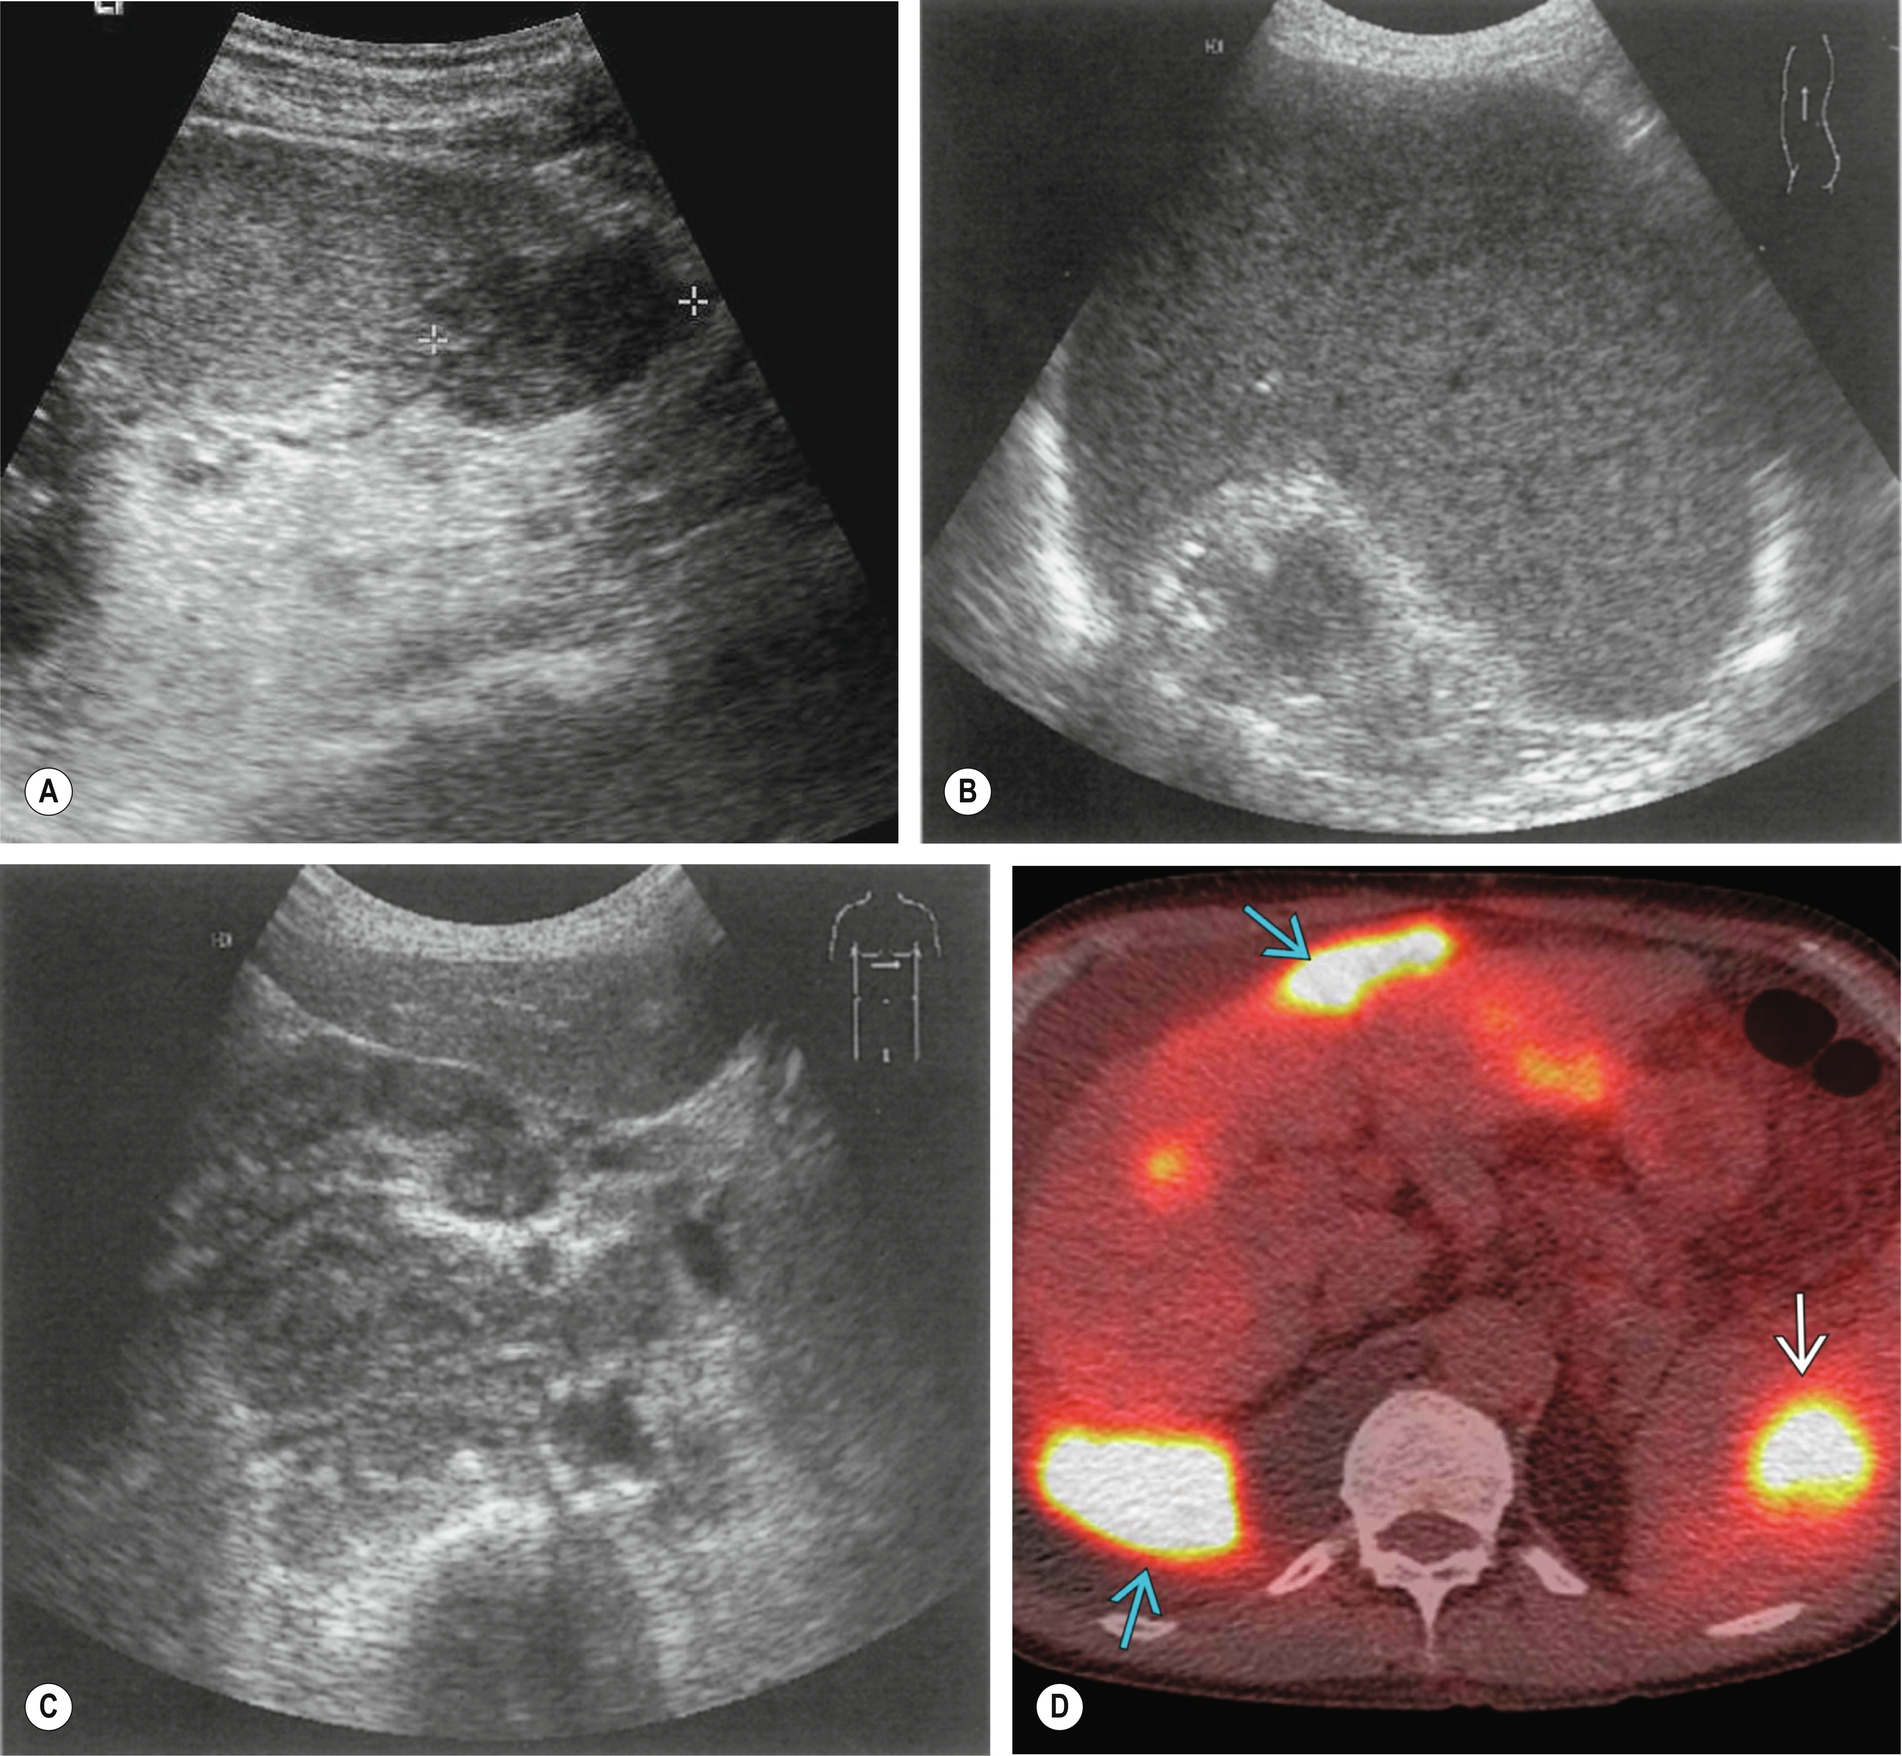

Lymphoma is the most common malignant disease affecting the spleen (Fig. 5.3). Malignant cells can infiltrate the spleen, lymph nodes, bone marrow, and thymus and can also involve the liver, gastrointestinal tract, kidney, and other organs. Approximately 3% of malignant diseases are lymphomas. However, a primary splenic lymphoma is rare, constituting 2% of all lymphomas and 1% of all non-Hodgkin’s lymphomas.6 A primary splenic lymphoma diagnosis is made when the lymphoma is contained within the spleen with no distant spread or only spread to the lymph nodes within the hilar region. Biopsy under ultrasound guidance can be performed and is considered a relatively safe procedure.

Lymphoma is also associated with acquired immunodeficiency syndrome (AIDS), and infection with human immunodeficiency virus (HIV) has given rise to a broad spectrum of lymphomatous conditions, which may be demonstrated on ultrasound and computed tomography (CT).8 These include masses in the liver, spleen, kidneys, adrenal gland, bowel, and other retroperitoneal and nodal masses. In addition, the increased use of immunosuppression in transplant patients and the increased survival in this group have also been the cause of an increased incidence of immunodeficiency-related lymphoma known as post-transplantation lymphoproliferative disorder (PTLD) (Fig. 5.3E).

Patients may present with a varied and broad spectrum of appearances in lymphoma (Fig. 5.3). In many cases, the spleen is not enlarged and shows no acoustic abnormality.11 Lymphoma may produce a diffuse splenic enlargement with normal, hypo-, or hyperechogenicity. In patients with hematological conditions, it is important to consider splenic volume as a way to show the progression of disease.

Although lymphoma usually has a diffuse effect on the spleen, focal lesions may also be present. They tend to be hypoechoic and hypovascular and may be single or multiple. In larger lesions, the margins may be ill-defined, and the echo contents vary from almost anechoic to heterogeneous, often with increased through transmission. In such cases, they may be similar in appearance to cysts. However, the well defined capsule is absent in lymphoma, which has a more indistinct margin.12 Smaller lesions may be hyperechoic or mixed. Tiny lymphomatous foci may affect the entire spleen, making it appear coarse in texture.

Lymphadenopathy may be present elsewhere in the abdomen. If other organs, such as the kidney or liver, are affected, the appearances of mass lesions vary but are commonly hypoechoic or of mixed echo pattern.

A differential diagnosis of metastases should be considered in the presence of multiple solid hypoechoic splenic lesions, but most cases are because of lymphoma. In patients who are immunocompromised and at risk from PTLD, the main differential diagnosis with multiple hepatic or splenic lesions would be abscesses, as both PTLD and abscess may have similar acoustic characteristics.

As with liver metastases, the ultrasound appearances vary enormously, ranging from hypo- to hyperechogenic or of a mixed pattern (Fig. 5.4). They may be solitary, multiple, or diffusely infiltrative, giving a coarse echo pattern. Metastases are usually solid in appearance. When cystic components are seen, this could indicate central necrosis or that the primary tumor is mucinous in nature (e.g., ovarian carcinoma).13

Splenic cysts have a relatively low incidence but are nevertheless the most common benign mass found in the spleen (Fig. 5.4D). Typically, cysts are rounded, with a thin wall with no internal echoes and posterior enhancement; occasionally thin septations may be seen, and also debris because of hemorrhage. Splenic cysts may occasionally be associated with autosomal dominant polycystic disease.